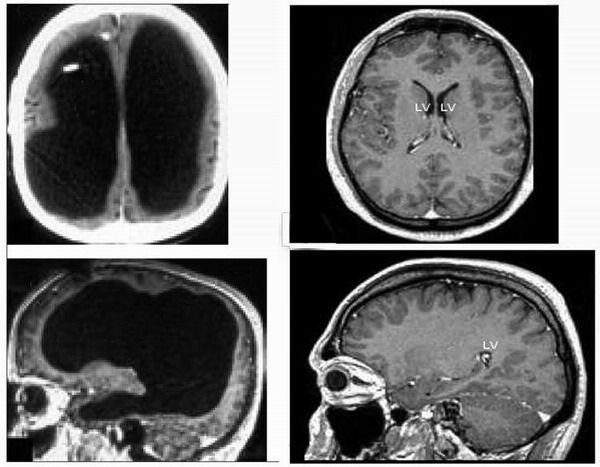

Совсем недавно, в июле 2007 года, в авторитетнейшем медицинском научном журнале «Lancet» была опубликована небольшая статья «Мозг клерка». В ней рассказывалось о поразительном случае гидроцефалии у французского клерка. Этот человек обратился в госпиталь Марселя с жалобами на слабость левой ноги, однако, когда ему сделали томографию мозга, то врачи, увидевшие снимки, были шокированы. Оказалось, что у этого мужика почти три четверти головного мозга отсутствовали. А он живет и работает. Фото его черепа в начале статьи. Его вербальный IQ был равен 84, что вполне сравнимо, к примеру, с IQ президента США Джорджа Буша младшего, у которого он, как говорят, был равен 91. Клерк жил обычной жизнью: исправно ходил на службу, был женат и имел двоих детей. Если бы у него не возникли проблемы с ногой, то никто бы и не узнал, что в его голове большую часть «жилой площади» занимает не мозг, а спинномозговая жидкость (ликвор).

Я томографию черепа не делал, а вдруг и я спиной думаю? Толерантнее надо быть, господа, толерантнее… Для сравнения, на фото справа показан типичный человеческий мозг в тех же проекциях. Фото: Feuillet et al./The Lancet.